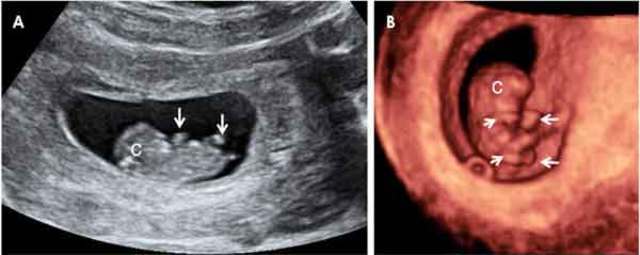

• Hernia del cordón umbilical

Hernia del cordón umbilical

SEMANA 6

• Regresa la hernia fisiológica

SEMANA 12